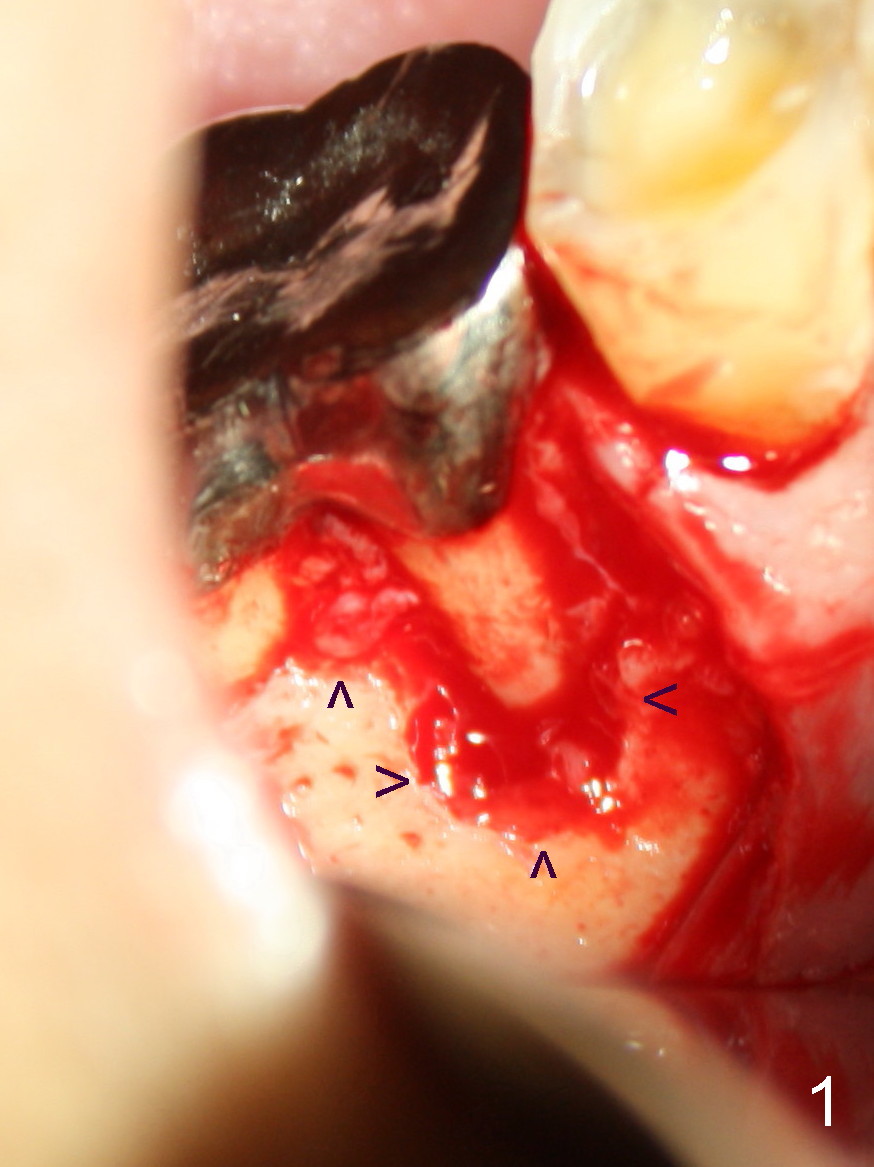

犹豫一阵子,最后决定采纳牙龈沟以及附加切口,翻瓣发现这个决策是英明(吹牛;至少视野好):右下第一磨牙整个近中根颊侧没有骨质覆盖,肉芽组织分布于根尖周围以及根分叉(图一箭头),与术前根尖片(图二)和根管治疗之前CT(图三:M:近中;D:远中)一致,心花怒放,一头栽入根尖切除术,心想病人有救了,尽管还背着黑锅:根尖炎加剧是根管治疗不妥所致。手术接近完成时,突然发现本人意料不到情况,您们猜是什么?提示多研究图一。不好意思,没有想考同学,不过想让大伙多多体验在美单枪匹马滋味(随时随刻作出判断,观察力要好)。不久见!